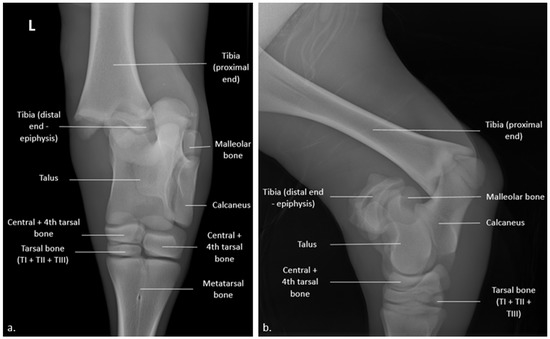

2. Case Presentation